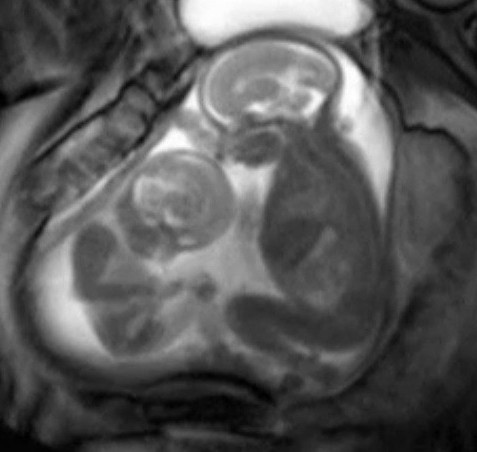

Egy várandós hölgy elképesztő dolgot látott az MRI felvételen!

Az MRI rendkívül pontos képet ad a méhben növekvő magzatokról. Ennek nagyon komoly jelentősége

van akkor, ha az anyuka egyszerre több magzattal terhes, ugyanis ilyenkor a komplikációk esélye is

nagyobb.

Az alábbi felvételen az látható, hogy a két tündéri gyermek az anyjuk méhében birkózik egymással. Az

orvosok szerint ez teljesen normális viselkedés